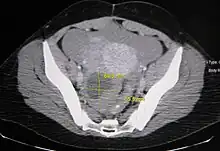

Ovarian cysts are usually diagnosed by ultrasound, CT scan, or MRI, and correlated with clinical presentation and endocrinologic tests as appropriate.[10]

Follow-up imaging in women of reproductive age for incidentally discovered simple cysts on ultrasound is not needed until 5 cm, as these are usually normal ovarian follicles. Simple cysts 5 to 7 cm in premenopausal females should be followed yearly. Simple cysts larger than 7 cm require further imaging with MRI or surgical assessment. Because they are large, they cannot be reliably assessed by ultrasound alone; it can be difficult to see posterior wall soft tissue nodularity or thickened septation due to limited ultrasound beam penetrance at this size and depth. For the corpus luteum, a dominant ovulating follicle that typically appears as a cyst with circumferentially thickened walls and crenulated inner margins, follow up is not needed if the cyst is less than 3 cm in diameter. In postmenopausal patients, any simple cyst greater than 1 cm but less than 7 cm needs yearly follow-up, while those greater than 7 cm need MRI or surgical evaluation, similar to reproductive age females.[11]

For incidentally discovered dermoids, diagnosed on ultrasound by their pathognomonic echogenic fat, either surgical removal or yearly follow up is indicated, regardless of patient age. For peritoneal inclusion cysts, which have a crumpled tissue-paper appearance and tend to follow the contour of adjacent organs, follow up is based on clinical history. Hydrosalpinx, or fallopian tube dilation, can be mistaken for an ovarian cyst due to its anechoic appearance. Follow-up for this is also based on clinical presentation.[11]

For multiloculate cysts with thin septation less than 3 mm, surgical evaluation is recommended. The presence of multiloculation suggests a neoplasm, although the thin septation implies that the neoplasm is benign. For any thickened septation, nodularity, vascular flow on color doppler, or growth over several ultrasounds, surgical removal may be considered due to concern of cancer.[11]